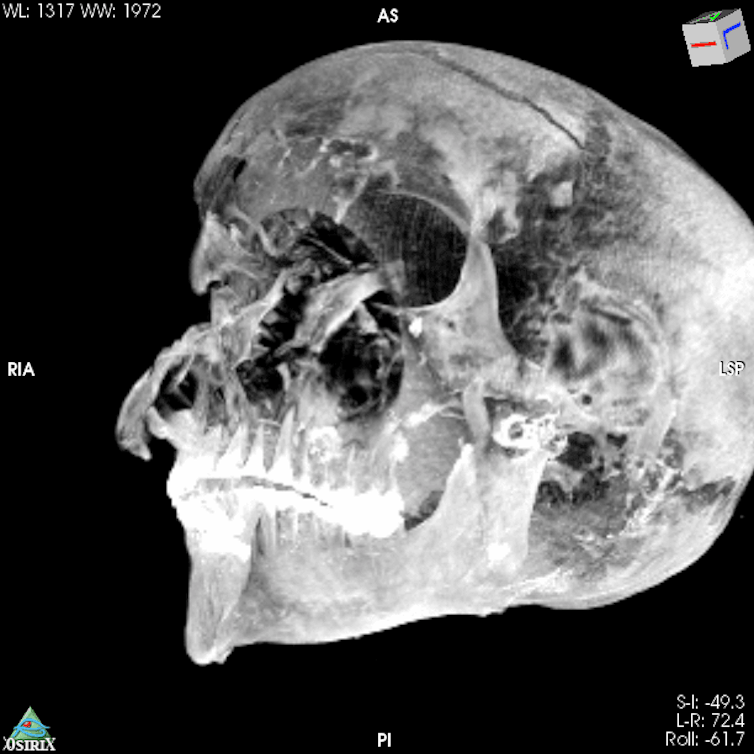

In the new study, the team applied computed tomography (CT) scanning to the remains to investigate further. CT is a non-invasive imaging method that basically layers multiple X-rays on top of each other in order to create three dimensional images of both the soft and hard tissues. We usually think of it in clinical settings, but it has a long history of use in forensic contexts to safely study remains contained inside wrappings or body bags.

The CT scans revealed the body was not arranged in its usual anatomical position. Even though it was in an unusual state, skeletal and dental indicators confirmed an age of around 40 years. Images of inside the skull confirmed that no attempt had been made to remove the brain. The CT examination revealed the extent of Seqenenre’s injuries, with a cut across the right side of his forehead, a puncture wound just above his right eye, a fractured nose and cheekbone, a cut on the left cheek area, fractures above his right ear, and a fracture of the bone inside his skull that runs behind the eyes.

Seqenenre suffered an incredibly violent death. The angle of the injuries suggested the attackers were positioned higher, so either on horseback or while he was kneeling, and facing him. The CT imaging allowed the shape of the wounds to be determined, showing that multiple weapons were used by multiple attackers. Yet such violent cranial injuries are usually accompanied by defence injuries on the arms as the victim attempts to defend himself. The CT scans confirmed that no such injuries were present here.